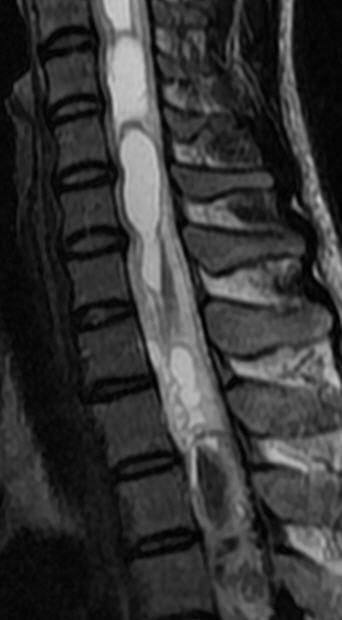

MRI

可提供腰椎管的矢状面、冠状面和轴位横断面上的影像。椎管狭窄以T2加权像显示较好,脑脊液为高信号,产生所谓“脊髓造影”的效果,而骨质增生,骨赘、间盘均为低信号,能清晰地显示椎管狭窄,以及对脊髓的压迫情况。但对肥大的黄韧带、骨质增生等的判断则不如较高清晰度CT扫描。

腰椎正常MRI解剖。

腰椎管狭窄MRI表现。